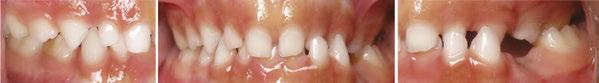

This patient presented in mixed dentition and a Class I occlusion with mild upper spacing, lower moderate crowding, and mild deep bite. The U3s were ectopic with a palatal position and a mesial path of eruption, converging onto the U2 roots, and the patient also had a tapered upper archform, an ovoid lower

archform, and a posterior tongue tie (mid-tongue restriction). The upper midline was centered with the facial midline, but the lower midline was deviated 4 mm to the left of the upper (Figure 1).

Figure 1: JA initial photos. Mixed dentition, Class I, upper spacing, lower crowding, ectopic U3s (10.7 years old)